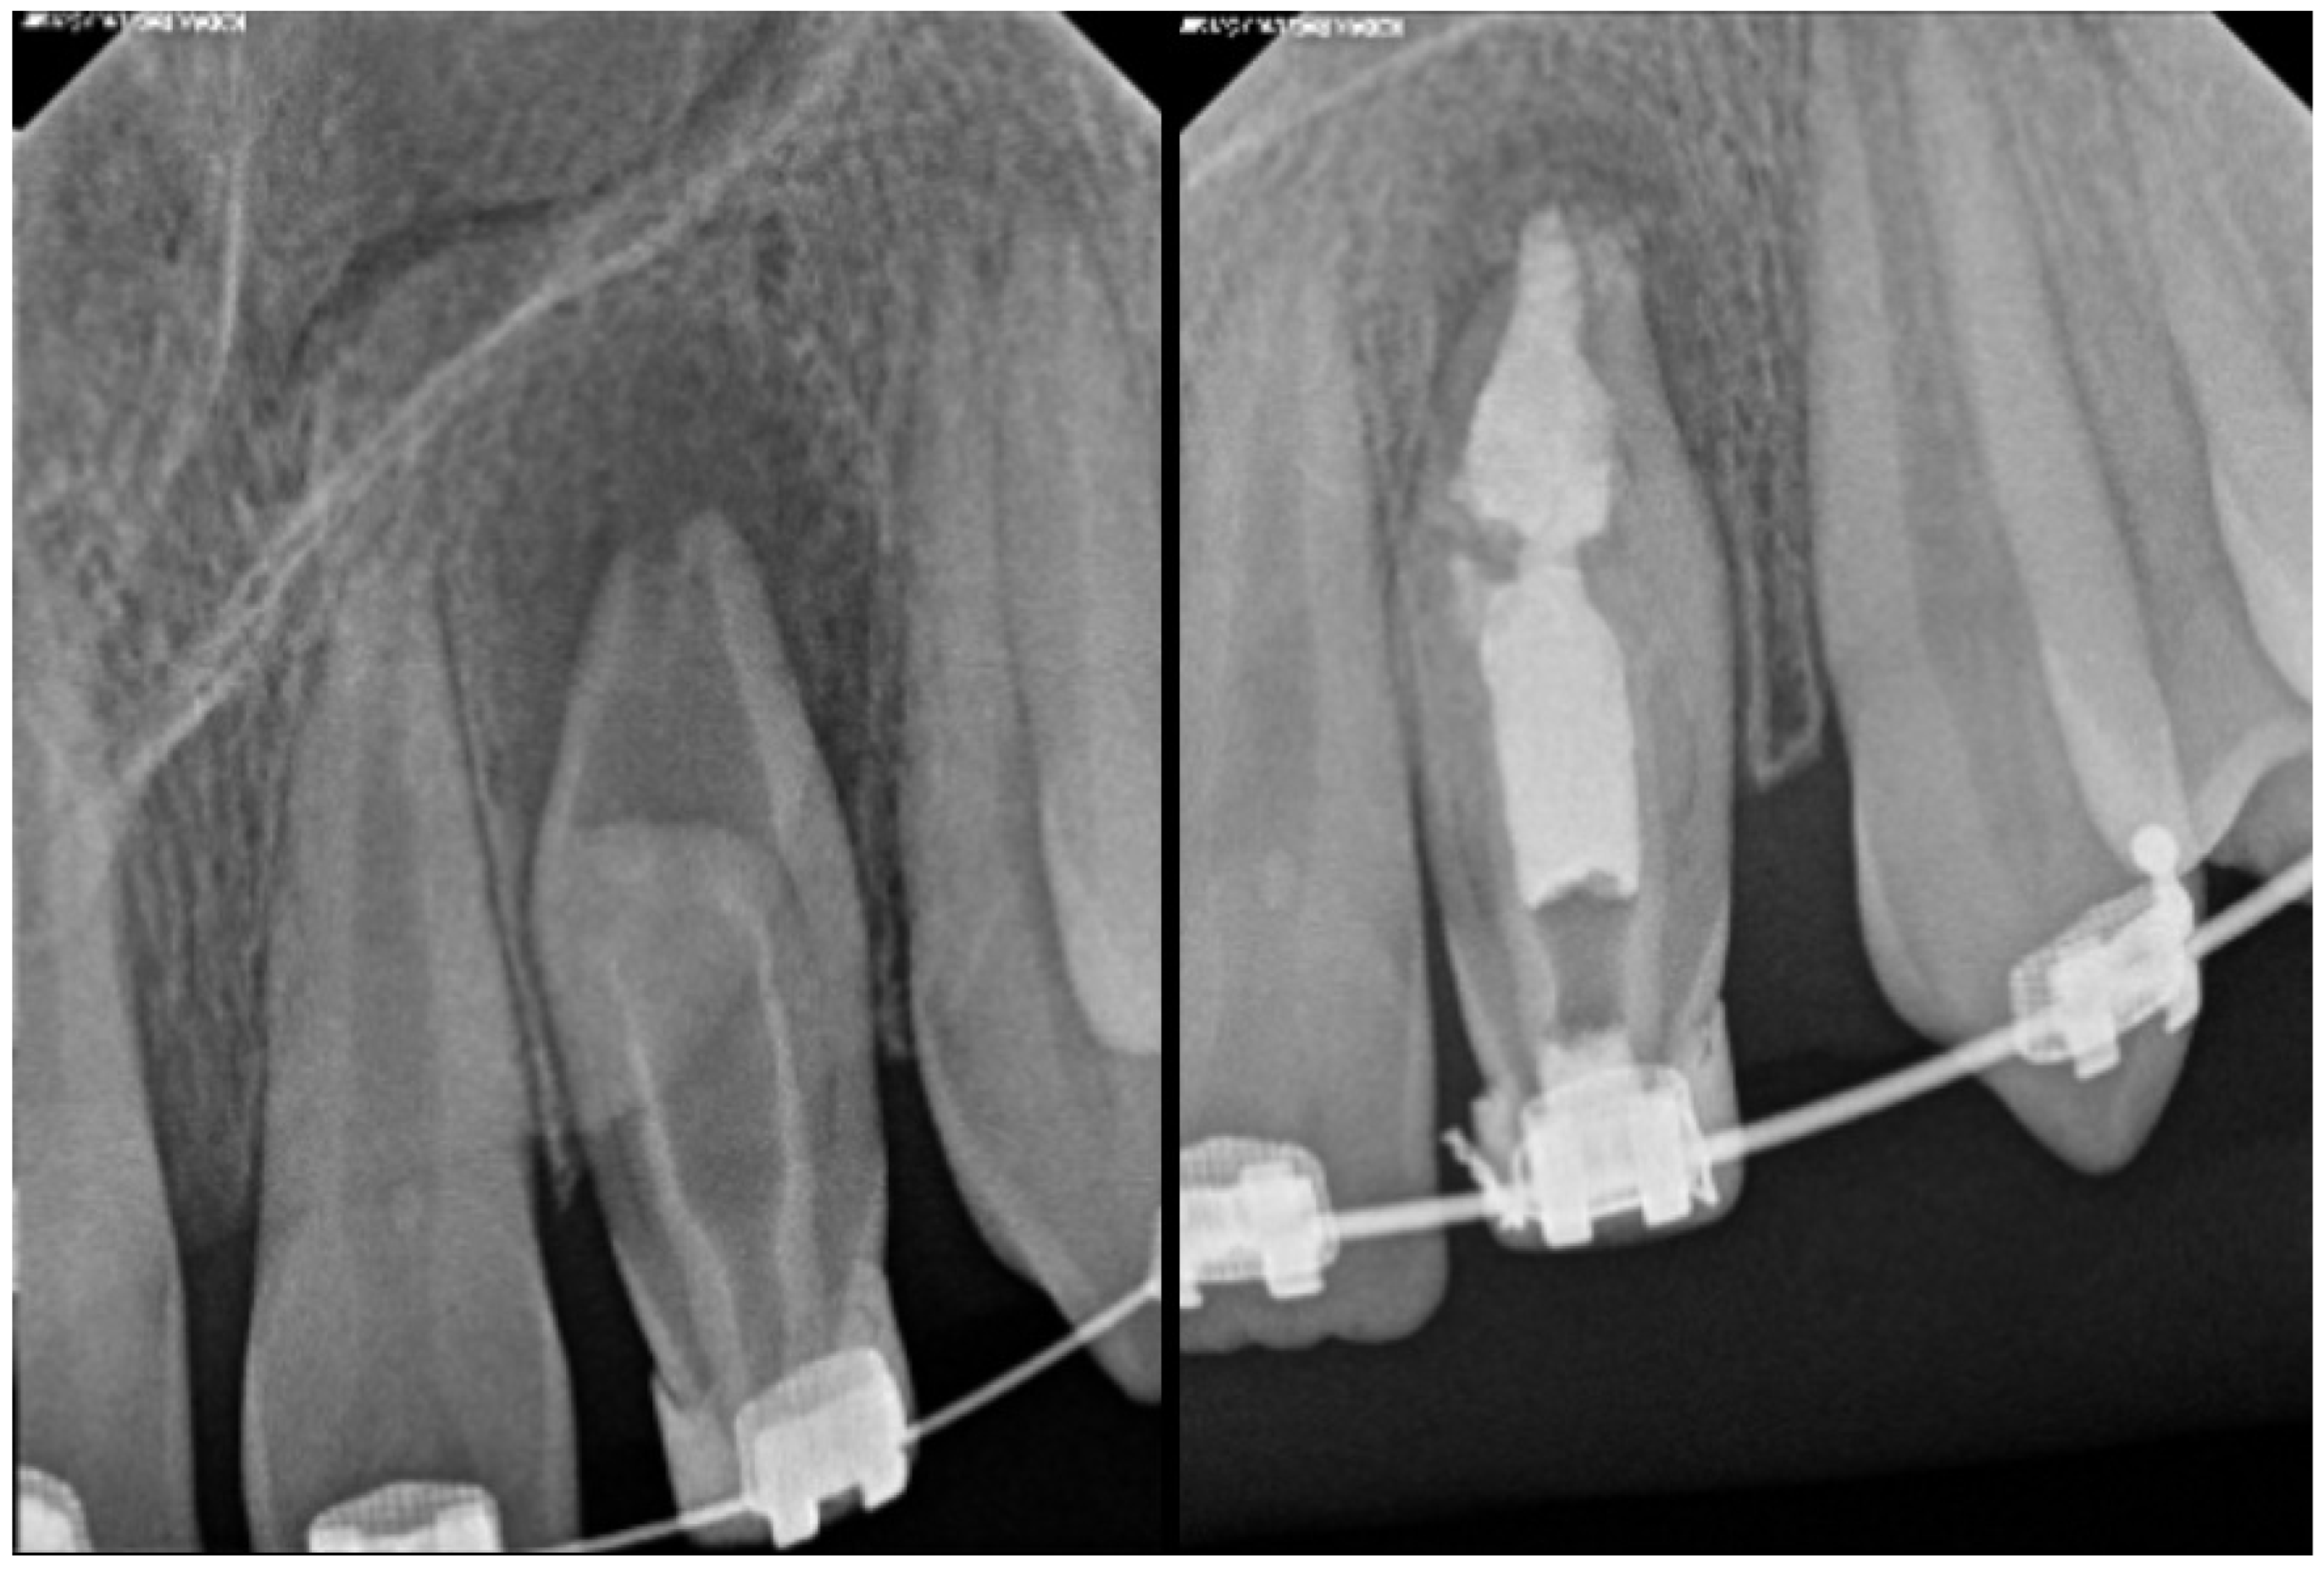

- Pires, M.D.; Baruwa, A.O.; Martins, J.N.; Quaresma, S.A.; da Costa, R.P.; Ginjeira, A. Endodontic management of developmental anomalies: Conservation of invaginated tissues in Type II dens invaginatus–case series. Rev. Port. Estomatol. Med. Dent. Cir. Maxilofac. 2019, 60, 18–26. [Google Scholar] [CrossRef]

| Type II | Moderate to high risk of pulp involvement | CBCT recommended to assess depth and pulp communication | Preventive sealing or minimally invasive restoration If pulp compromised, vital pulp therapy or root canal treatment depending on health state of pulp | Good to fair prognosis if depth is within coronal third and detected early Radiographic follow-up needed to monitor healing |